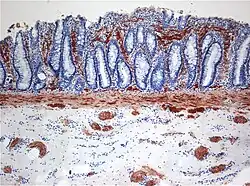

![]() | |

| Histopathology of Hirschsprung disease showing abnormal acetylcholine esterase (AchE)-positive nerve fibers (brown) in the mucosa | |